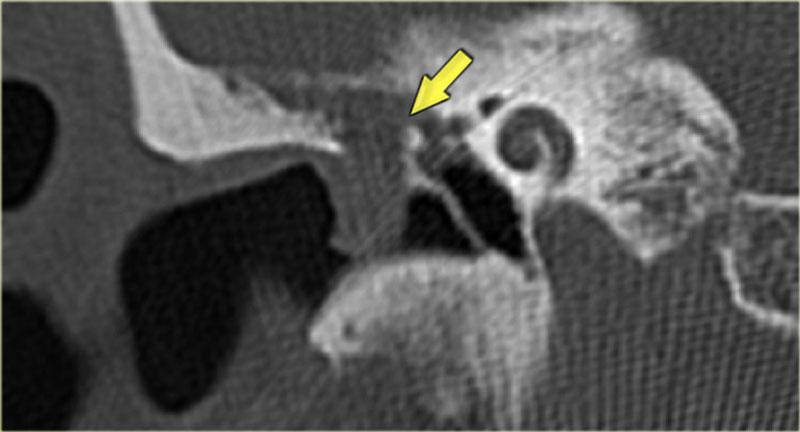

Bên trái là hình ảnh của một bé trai 2 tuổi với teo ống tai ngoài xương hai bên.

Xương búa và xương đe hợp nhất (mũi tên).

Ốc tai bình thường.